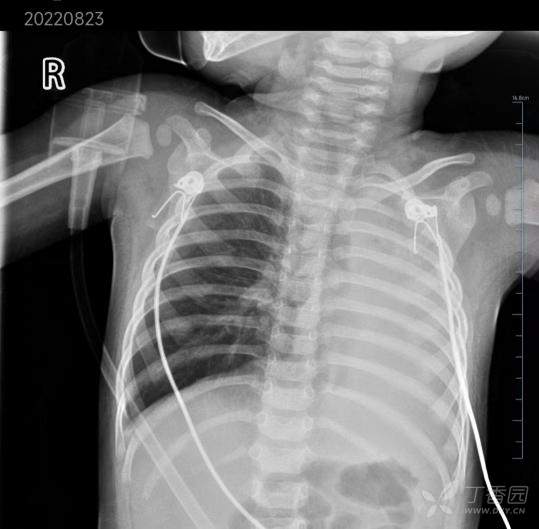

患儿,男,1 岁,2022.08.23 入院

主诉:咳嗽 2 天,发热 1 天

现病史:患儿 2 天前无明显诱因下出现咳嗽,为阵发性单声咳,不剧。1 天前咳嗽加重,频率较前增多,出现发热,体温最高 38.7℃,无畏寒寒战,无气促发绀,无呼吸困难,无烦躁不安,无嗜睡,无呕吐腹泻等,至当地市儿童医院就诊,予「拉氧头孢钠、盐酸氨溴素静滴、复方福尔可定口服溶液口服等对症治疗」,症状未见明显好转,夜间出现呼吸急促,嘴唇发绀,烦躁不安,遂住院治疗,查 CT,如下图所示:

全白的左肺

考虑「呼吸衰竭,支气管肺炎」,予「头孢他啶静滴抗感染,甲强龙抗炎平喘,雾化等对症治疗」,患儿病情进行性加重,出现呻吟、面色苍白、精神反应差,面罩吸氧 5L/min下血氧饱和度维持 90% 左右,为进一步诊治,120 转来我院,急诊拟「重症肺炎、呼吸衰竭」收住 ICU。

入院时查体:T 37.0℃,P 150 次/分,R 34 次/分,BP 97/56 mmHg,危重评分 88分 ,营养评分 0 分,GCS评分 11 分。面罩吸氧(流量 6 L/min)SPO2 仅维持 85-90%,精神差,无皮疹,颈软,双侧颈部未触及肿大淋巴结,呼吸急促,可见明显三凹征,左侧呼吸音消失,未闻及湿啰音;心律齐,心音中等,未闻及明显杂音,未及震颤;腹平软,肝脾肋下无肿大;心神经系统查体阴性,肌张力、肌力正常,CRT 2s。

8.23 肺部 CT 如图: